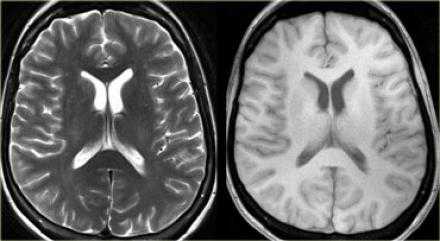

На PD/T2WI и FLAIR выглядит гиперинтенсивно. На PD/T2WI и FLAIR последовательностях возможно диагностировать до 80% инфарктов впервые 24 часа, но впервые 2-4 часа после инсульта изображение также может быть неоднозначным. На PD/T2WI и FLAIR продемонстрировано гиперинтенсивность в районе левой средней мозговой артерии. Обратите внимание на вовлечение в процесс лентиформного ядра и островковой доли. Область с гиперинтенсивным сигналом на PD/T2WI и FLAIR соответствует гиподенсивной области на КТ, что в свою очередь прямой признак гибели клеток мозга.

Когда мы сравниваем результаты на T2WI и DWI во времени, мы заметим следующее: В острой фазе T2WI норма, но со временем зона инфаркта станет гиперинтенсивной. Гиперинтенсивность на T2WI достигает своего максимума между 7 и 30 дней. После этого сигнал начинает угасать. На DWI гиперинтенсивная область в острой фазе, а затем становится более интенсивной с максимумом на 7 дней. На DWI у пациента с инфарктом головного мозга визуализируется гиперинтенсивная область примерно на 3 недели после начала заболевания (при инфаркте спинного мозга на DWI визуализируется гиперинтенсивная область на одну неделю!). На ADC будет сигнал низкой интенсивности с минимальной интенсивностью в первые 24 часа, после сигнал будет увеличиваться в интенсивности и, наконец, становится максимально интенсивным в хроническую стадию.

Прежде считалось, что гиперинтенсивный сигнал на DWI — это мертвые ткани. Новейшие исследования доказывают, что некоторые очаги из них вероятно могут быть потенциально обратимым повреждениям. Это наглядно показано, если сравнить изображения одного и того же пациента DWI в острейшую фазу и Т2WI в хроническую фазу. Размер поражения на DWI намного больше.